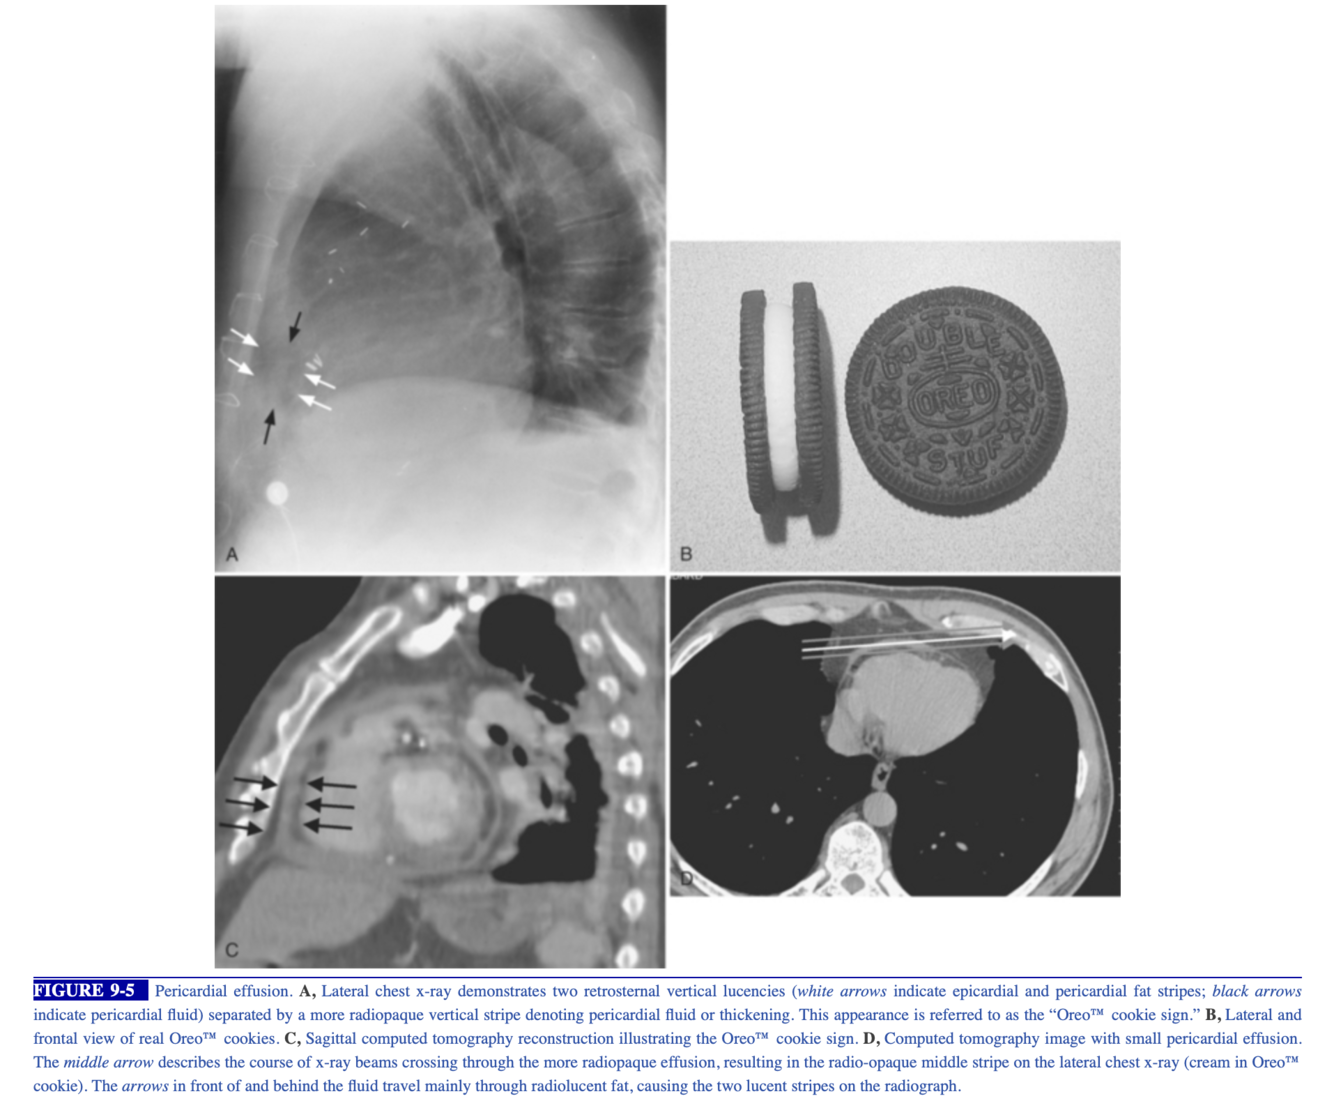

Radiographic Features ( Fig. 2.80 )

Vertical retrosternal opaque stripes representative of possible pericardial effusion (“oreo cookie sign”).